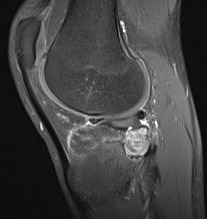

MRI

Rarely diagnostic

- high signal intensity on T2